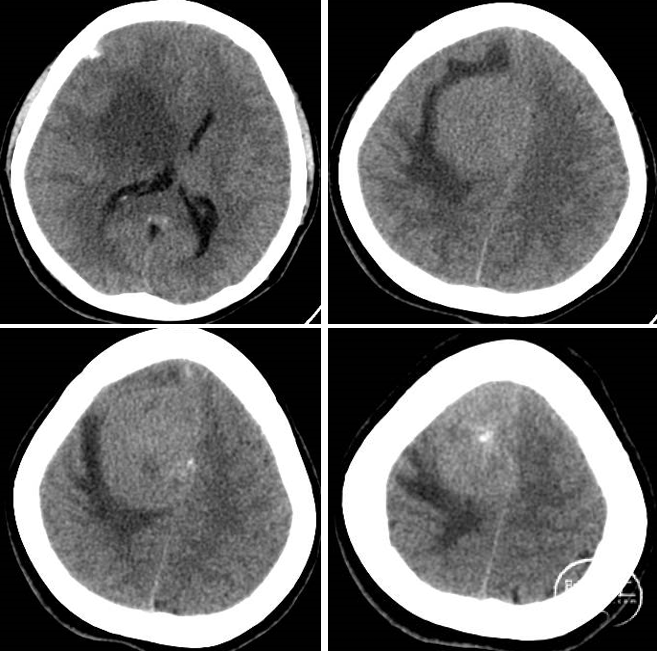

现病史:患者2020年无明显诱因出现头痛,患者未予以重视及相关诊疗。2周前患者出现左侧肢体活动障碍,伴肢体麻木,遂于2023年9月19日就诊于当地医院,行颅脑CT检查示:“右侧顶部大脑廉旁见混杂密度影,边界清,大小约6.0cm×4.4cm,周围见低密度水肿,脑中线左移,脑沟及脑室系统未见特殊,提示:右顶部占位,脑膜瘤可能性大,建议进一步检查”。现为求手术治疗,转至我院。

术前CT